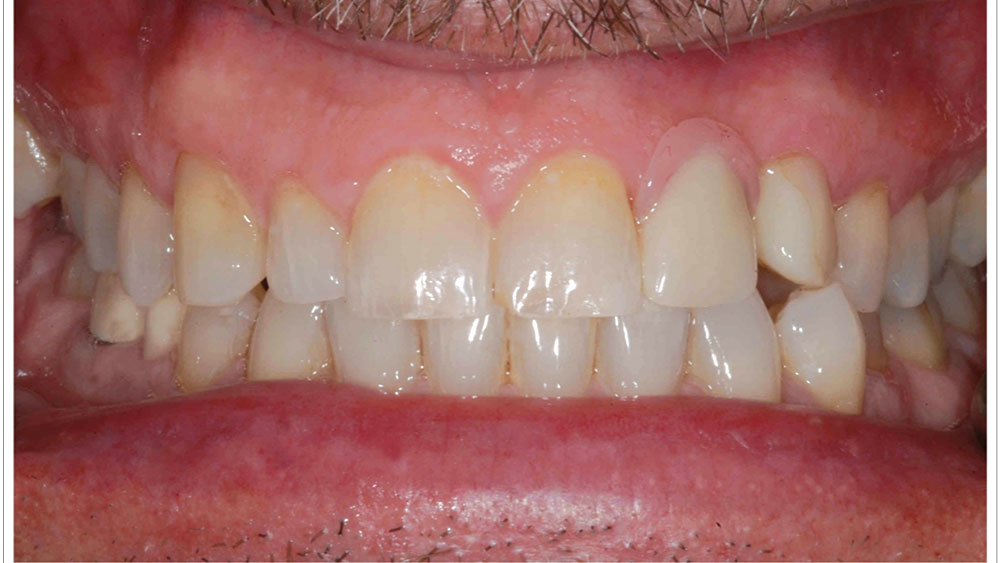

When placing implants in the esthetic zone, it is important to understand and manage your patients’ expectations. I always tell patients that all restorations in the anterior are difficult — whether implant or traditional crown & bridge — due to challenges with matching the shade and characterization of adjacent teeth. I suggest letting patients know that the restoration will look great, but when they look at it very closely, they may notice a difference. It’s also a good idea to begin with patients who have been part of your practice for some time, as the rapport that you have developed with them often makes it easier to comprehend and meet their expectations.

For the first few anterior cases, you should select clinical situations in which an untreatable tooth is removed, the extraction site is grafted, and the implant is placed after several months of healing. This approach allows you to develop the ideal soft-tissue contours and bone volume needed for straightforward implant surgery and a predictable outcome. Until you have more experience, I would not suggest extraction with immediate implant placement — unless you have Dr. Jack Hahn standing by your side! It’s also important to select patients who have favorable teeth alignment as well as a thick tissue biotype, both of which make it easier to achieve a natural emergence profile and esthetic result. High smile lines should be avoided.

• Select favorable tooth alignment

• Look for thick tissue biotype